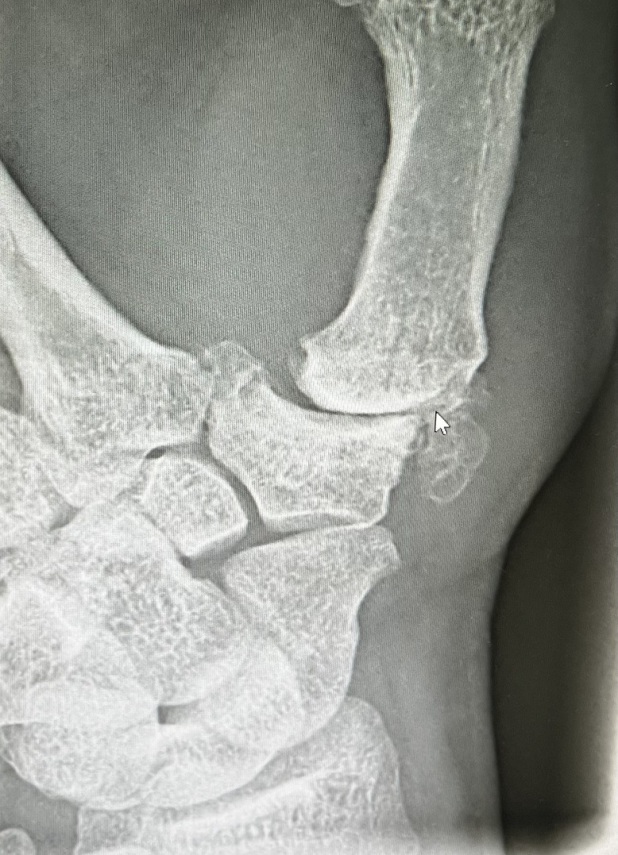

Sattelgelenkprothese Typ Touch

In unserer Praxisklinik wir bei einer Arthrose im Sattelgelenk als ein sehr erfolgreiches Verfahren eine Prothese in das Daumensattelgelen eingebaut. Wir verwenden ein sehr gutes Impantat von der Firma Medartis und zwar die Touch Prothese.